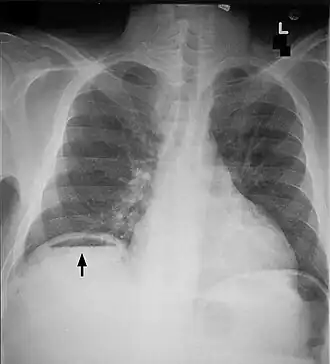

«Симптом серпа» под правым куполом диафрагмы | |

Симптом серпа, выявляемый между правым куполом диафрагмы и печенью при исследовании органов брюшной полости — признак перфорации полого органа брюшной полости (желудка или кишки), связан с поступлением газа в брюшную полость.